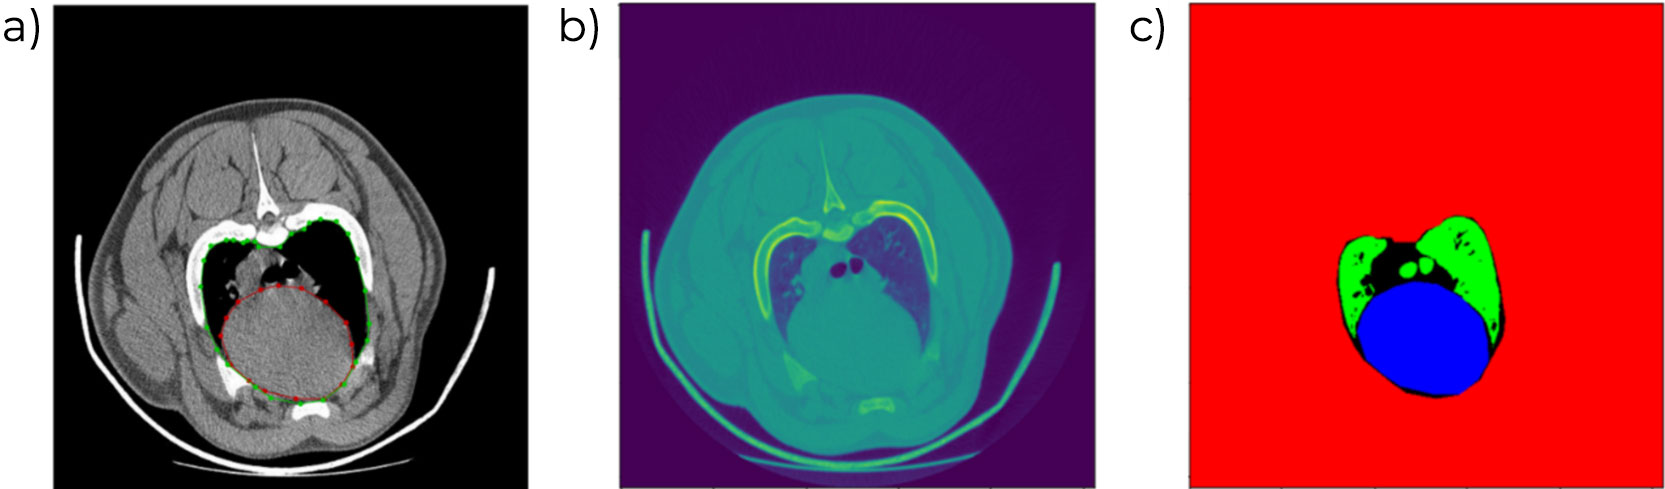

A presença de lesões na cabeça do fêmur e do úmero, para identificar processos de artrite ou osteocondrose. Essa avaliação faz parte do objetivo de seleção de todas as linhas genéticas. O processo inclui uma etapa manual, que em breve será substituída por um processo automatizado de segmentação e quantificação das lesões, o que também permitirá incluir a avaliação de mais superfícies ósseas.

O tamanho e a forma da escápula têm sido avaliados e relacionados com a longevidade das fêmeas e com a presença de úlceras e outras lesões na paleta de fêmeas adultas.